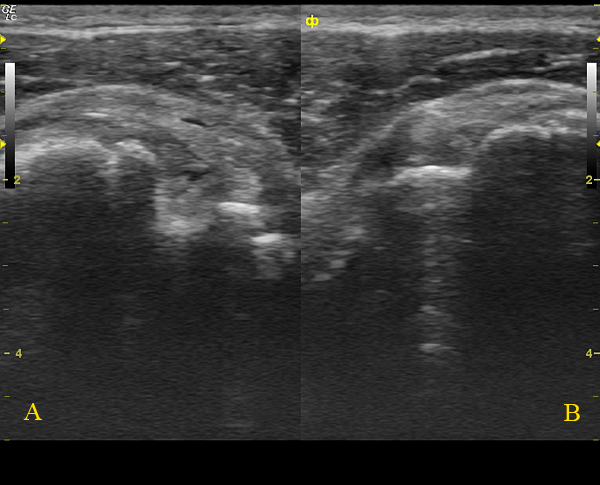

Да, на последней сонограмме В+В: А - сонограмма с патологией, В - таже проекция в здоровом противоположном плечевом суставе.